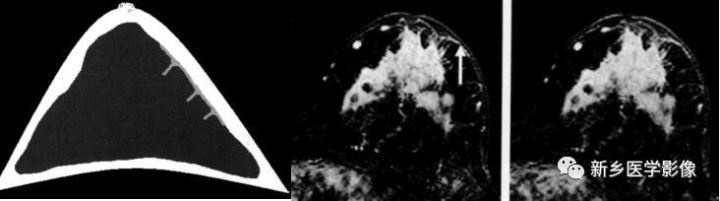

肺实变与肺不张的CT鉴别诊断